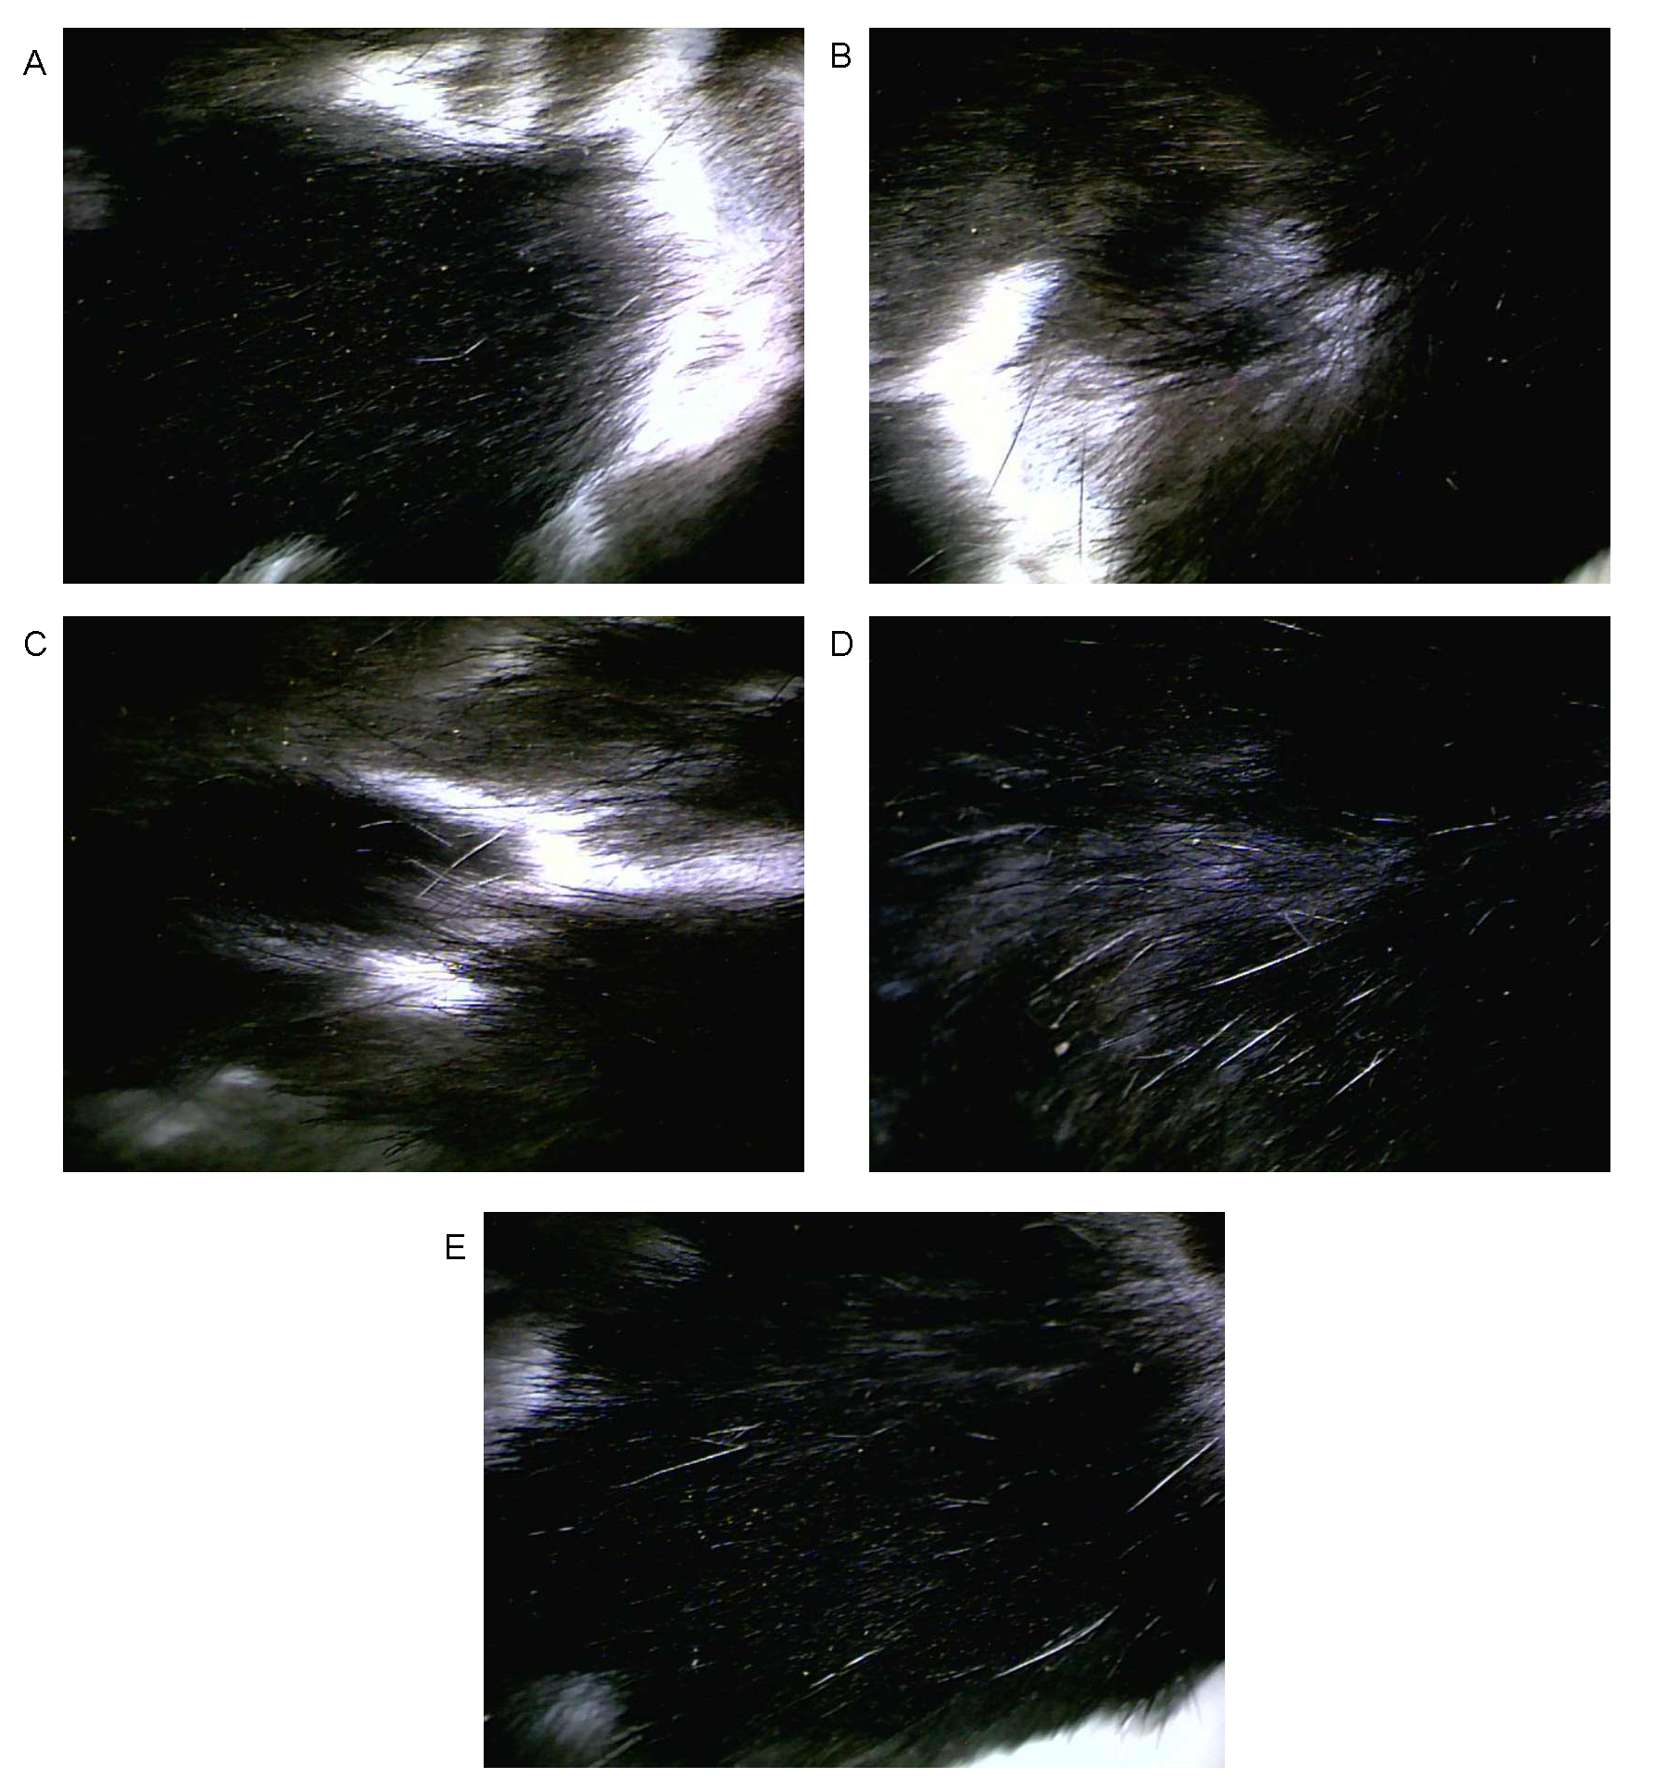

Hair growth promoting efficacy of the CT-NLC was assessed in the C57BL/6Mlac mice by the method reported by our group [12]. Briefly, twenty-five mice were randomly divided into five groups for the five treatments as followed: control, NLC blank, minoxidil, safflower extract, and CT-NLC. In the control group, DI water was used. In the NLC blank group, 5 % by weight of NLC base in DI water was used. In minoxidil group, 2% minoxidil in DI water was used. In safflower group, 0.1% by weight of safflower extract in DI water was used. In CT-NLC group, 5% by weight of CT-NLC in DI water was used. Prior to the experiment, the 3x4 cm (width (height) dorsal areas of seven-week-old mice were shaved by using a depilatory cream. On the next day, 100 µl of samples were applied gently on the mice back once daily, for 28 consecutive days. Hair growth promoting activities of tested components were assessed by observing the darkening of the skin and giving the hair growth score, as follows: score 0 = no growth observed; 1 = up to 20% growth; 2 = 20–40% growth; 3 = 40–60% growth; 4 = 60–80% growth; and 5 = 80% to full growth observed.

Digital images of total hair growth on day 28 were obtained using a Coscam® USB-225 (Seoul, South Korea) with a 40× magnification lenses.

The results on hair growth promoting activity of CT-NLC compared with the control, NLC base, minoxidil and crude safflower extract were shown in fig. 5. From fig. 5, CT-NLC and 1% safflower extract exert the strongest hair growth promoting activity, followed by 2% minoxidil and NLC blank. Water, which was used as control showed the normal hair growth rate of mice.

Total hair growth at day 28 was shown in fig. 6, which was obtained from Coscam, a special camera that used for viewing the skin. The pictures from Coscam suggested that the mice received CT-NLC, and 1% safflower extract had the highest hair growth. None of any irritation occurred in mice when treated with water, NLC base, CT-NLC or safflower extract.

Fig. 6: Total hair growth in C57BL/6 mice at day 28 where: (A) control (B) minoxidil treated (C) NLC base treated (D) safflower-loaded NLC (CT-NLC) treated and (E) safflower extract treated. Digital images obtained from Coscam® USB-225 with 40x magnification lens